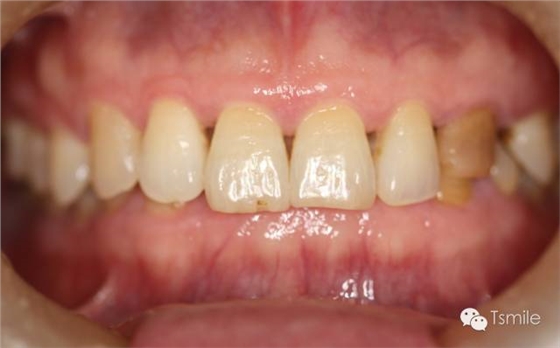

磨耗患者中還有一類(lèi)特殊的局限于上下前牙區(qū)的牙齒重度磨耗,表現(xiàn)為上前牙舌面、下前牙切端和唇面的重度磨耗。該類(lèi)患者常表現(xiàn)為一類(lèi)特殊的咬合類(lèi)型,重度深覆頜或者上前牙明顯舌傾,這種咬合類(lèi)型導(dǎo)致下頜前伸功能運(yùn)動(dòng)受限,從而導(dǎo)致前牙區(qū)重度的磨耗,可稱(chēng)為前牙功能范圍受限(restricted envelope of function)。

圖2: 前牙功能范圍受限導(dǎo)致的前牙重度磨耗 磨損是指在非下頜功能運(yùn)動(dòng)和副功能運(yùn)動(dòng)中,除牙齒以外的其它物體對(duì)牙齒表面機(jī)械摩擦而導(dǎo)致的牙齒表面硬組織缺損。 磨損患者一般有某種特殊的生活習(xí)慣或工作習(xí)慣,如不正確的刷牙方式、長(zhǎng)時(shí)間叼煙斗、咬指甲、咬鉛筆等生活和工作習(xí)慣。長(zhǎng)時(shí)間的不良習(xí)慣,這些煙斗、鉛筆、指甲等異物會(huì)對(duì)牙齒表面過(guò)度機(jī)械摩擦,導(dǎo)致牙齒表面硬組織缺損。